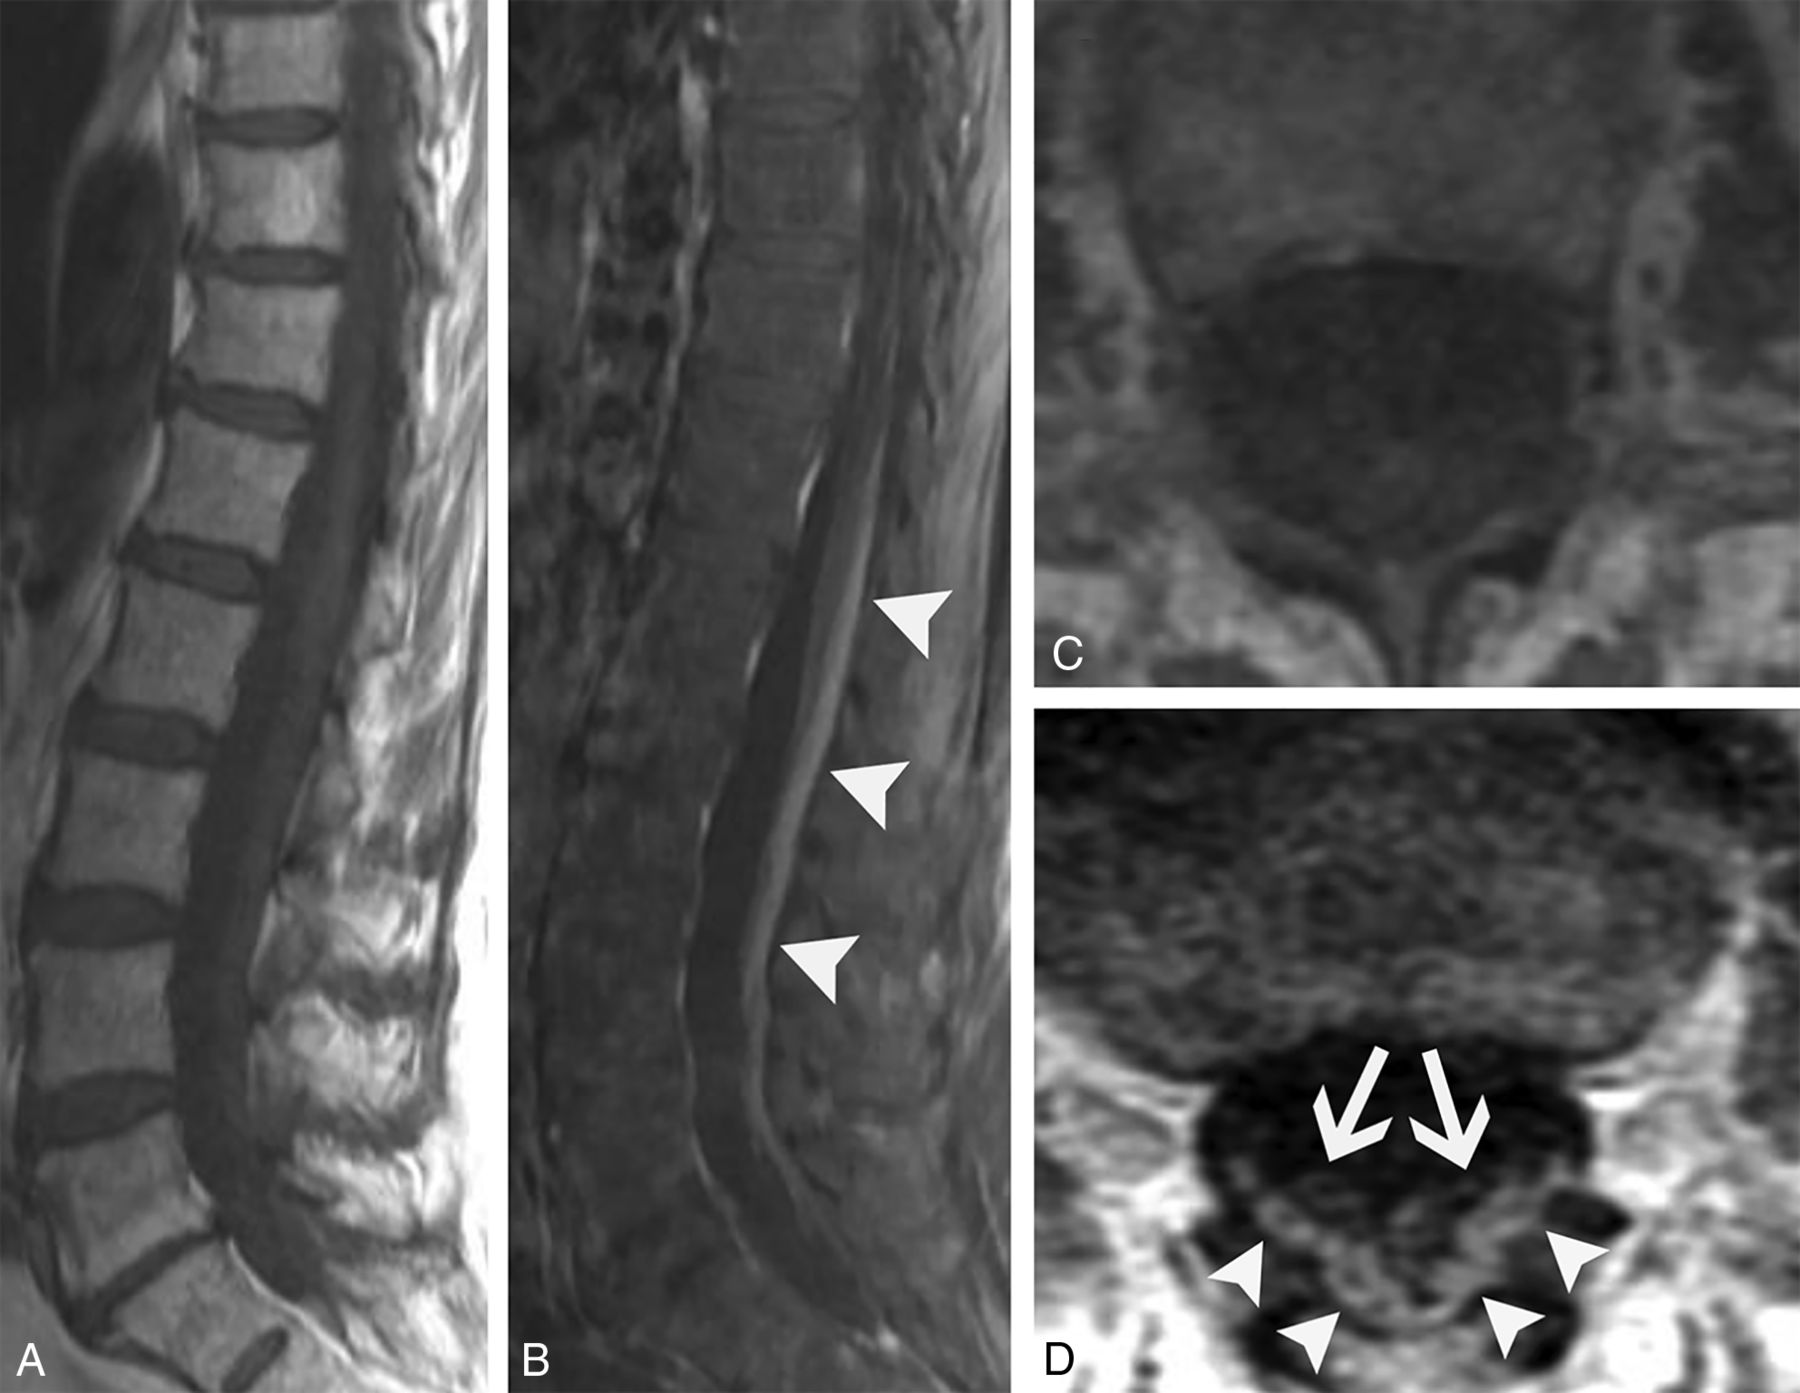

Paraneoplastic myelitis (A–E). A 52-year-old woman recently diagnosed with small cell lung cancer presented with progressive bilateral lower extremity weakness over weeks. Lumbar puncture was remarkable for elevated CSF IgG index and IgG synthesis rate, though no specific paraneoplastic antibody was identified. Sagittal T1-weighted pre- (A) and postcontrast (B) images and an axial postcontrast image (C) from her thoracic spine MR imaging show a long segment of enhancement involving the lateral columns of the thoracic spinal cord. Corresponding axial T2-weighted (D) and FDG-PET/CT (E) images show increased T2 signal (D, arrows) and marked abnormal FDG uptake (E, arrows) in the spinal cord. She was diagnosed with paraneoplastic myelopathy and had transient improvement with methylprednisolone. Paraneoplastic myelitis with treatment response (F–I). A 64-year-old woman recently diagnosed with small cell lung cancer presented with gait difficulties and progressive bilateral lower extremity weakness lasting several months. Serum and CSF were positive for CRMP5 autoantibodies. Sagittal T2-weighted (F) and axial T1-weighted postcontrast (G) images of the cervical cord show increased T2 signal (F, arrows) and enhancement of the lateral columns (G, arrows). She was treated with 6 months of cyclophosphamide and had partial symptomatic improvement. Follow-up sagittal T2-weighted image (H) shows near resolution of abnormal signal. There is mild residual patchy cord enhancement, greatest in the lateral columns (I, arrows).

In addition to the usual paraneoplastic work-up, MR imaging of the entire spine is particularly helpful in these patients because of the longitudinally extensive nature of spinal cord involvement. Imaging of the brain is also usually indicated to assess for associated encephalitis, which is frequently seen with anti-CRMP5 syndromes. Typical treatment includes management of the underlying malignancy and immunosuppression. Despite treatment, the outcome is overall poor with most patients becoming wheelchair dependent. Although follow-up of patients with paraneoplastic myelitis is not well documented in the literature, clinical improvement and improvement in imaging findings can occur (Fig 7F–I).